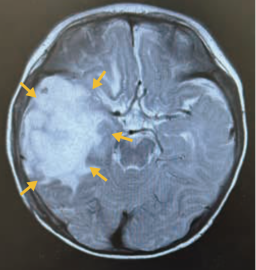

当院小児科初診時(20XX年Y-3月下旬)

頭部単純CT検査

頭部+全脊椎造影MRI検査

左:T2強調画像 右:T1強調画像

ヴァイトラックビ投与開始時

(20XX年Y月上旬)

- MRI画像上、ヴァイトラックビ投与2か月後に80%以上の腫瘍縮小を認め、7か月後も腫瘍縮小した状態を維持しており、初診時にみられた嘔吐の消失および左上肢麻痺の改善傾向も確認された